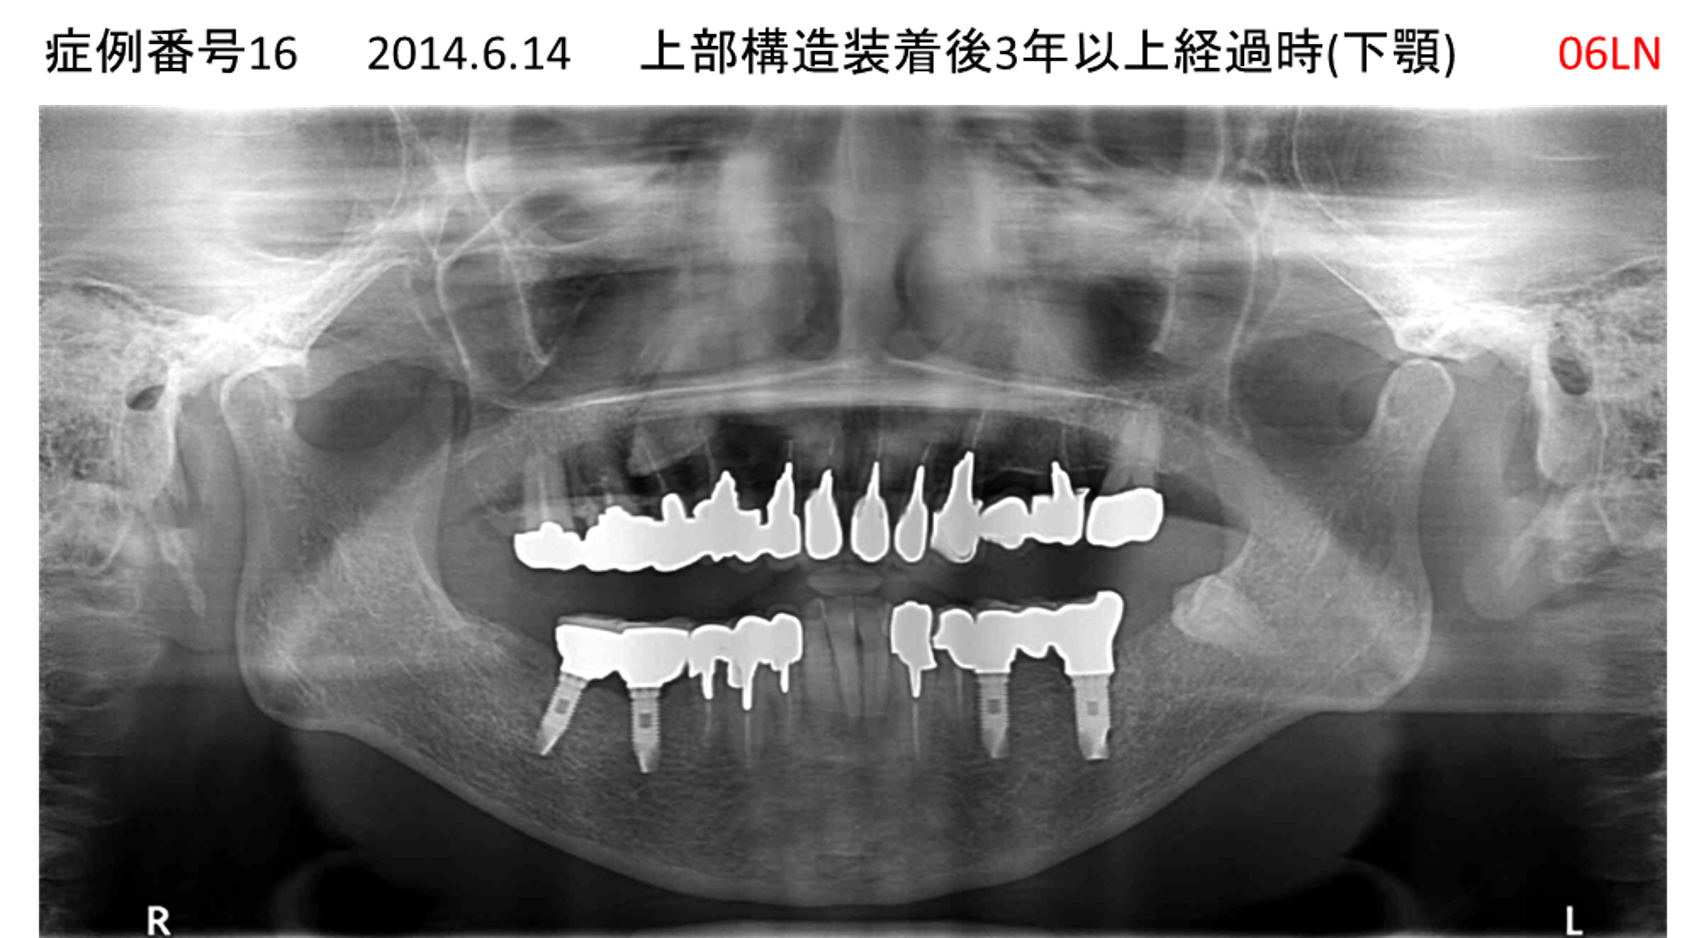

義歯が合わない、噛めない患者様のインプラント症例

| 治療名称 |

インプラントコーヌステレスコープ |

| 治療費用 |

270万円+税 |

| 治療期間 |

4か月 |

| 患者さんの症状(主訴) |

義歯が合わない、噛めない |

| 治療内容 |

インプラント、義歯作製(コーヌステレスコープ) |

| 治療結果 |

しっかり噛めるようになった。見栄えが良くなった。 |

| 治療の注意点(リスク/副作用) |

義歯が壊れた場合、インプラントが壊れた場合は再治療が必要 |